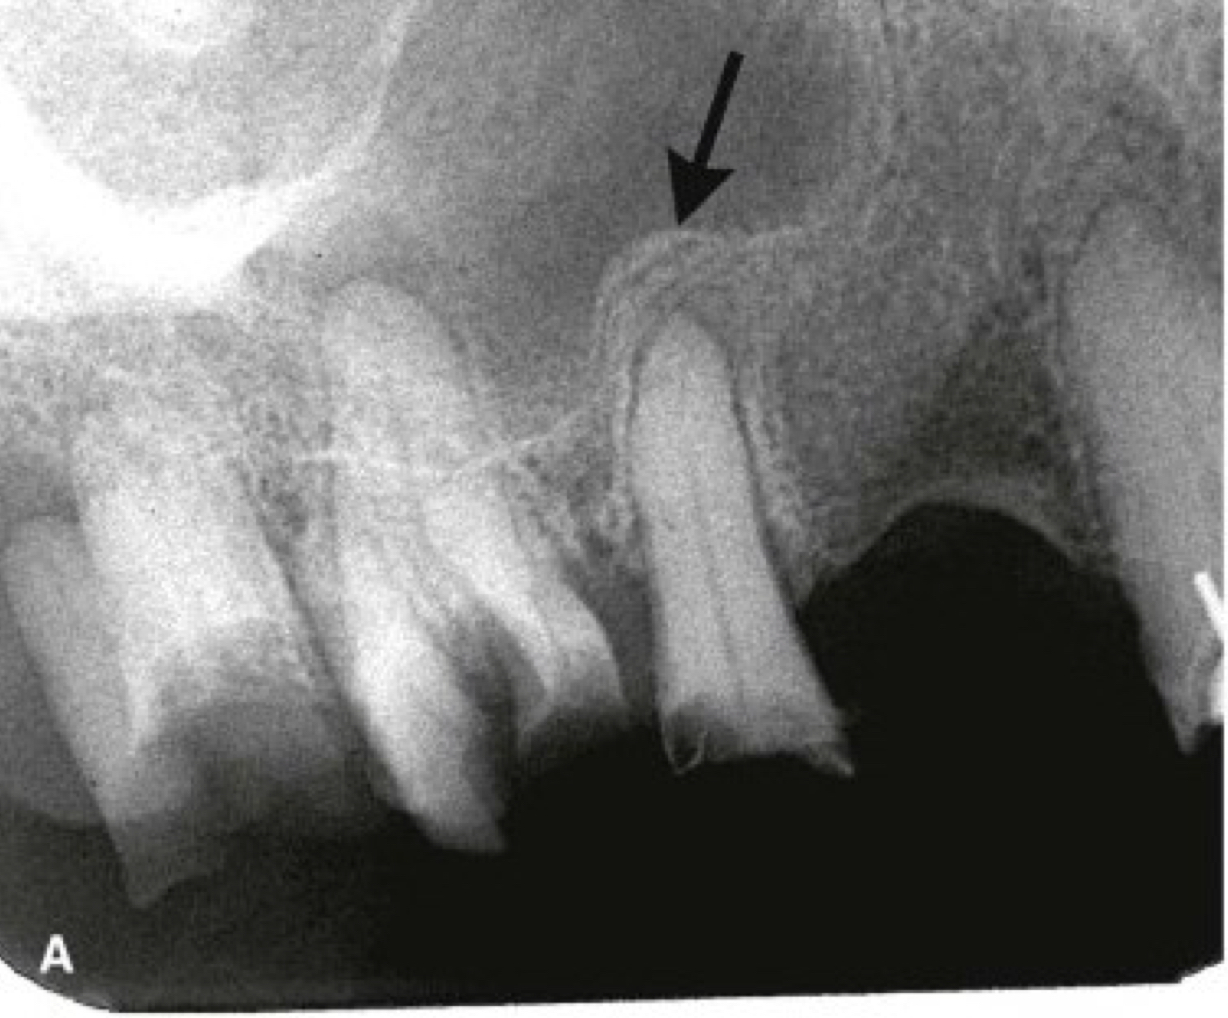

radiographic signs:

widened PDL space

loss of lamina dura

apical periodontitis

lack of continuous lamina dura, initial signÂ

apical periodontitisÂ

early periapical lesion

widening of PDL space, thickening of LD